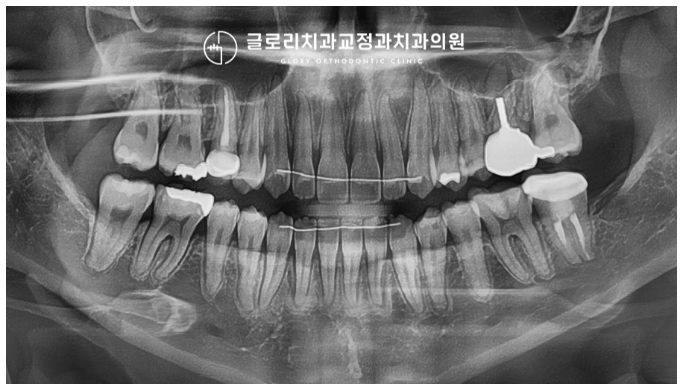

절단 교합 치료 과정

보통 이런 경우는 3급 부정교합과 함께 동반됩니다.

그렇기 때문에 원인을 정확히 파악하여

그에 맞는 치료 계획을 세우는 것이 중요한데요

대표적인 원인은 아래와 같습니다.

『1) 골격적인 문제

2) 앞니의 맹출 이상

3) 혀의 위치 이상』

이분의 경우 다행히 골격적인 문제는 아니었는데요.

따라서 중랑구교정치과 에서는

치열 개선을 진행하여 위, 아래 위치를

바로잡아주기로 계획을 세웠습니다.

배열 공간이 많이 필요하진 않았기 때문에

이를 뽑지 않는 비발치로 진행하기로 하였으며,

미니스크류를 사용하여 하악의 후방이동,

상악의 전방 이동을 유도하기로 했죠.